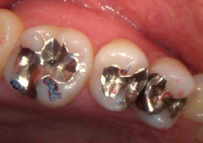

銀歯の除去後(むし歯が広がっています)、むし歯の除去と神経の保護